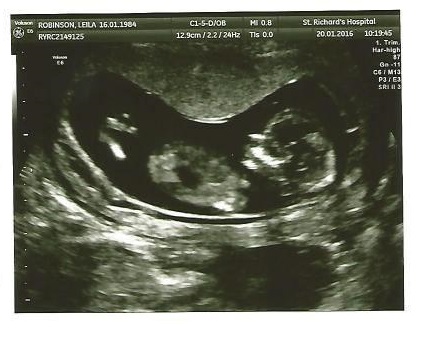

front view ultrasound

hi girls , this is 12 weeks 5 days ultrasound.unfortunately there is no clear pic from nub.but on the first one which is front view I can see 3 lines.Is it nub ?

sorry , I'm new .hope you can see it now.it's just a bit odd.because it looks like if that's nub , is not in right place.

Hmm I'm not sure I'm seeing a nub but if you asked me to guess I would say girl since what I am seeing looks flat. This is a hard one though:/

I'm thinking girl from the 2nd pic... assuming that is the nub I can see.